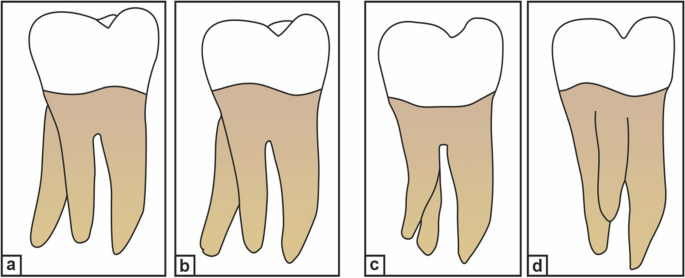

Carlsen and Alexandersen4 (Fig. 1), Ribeiro and Consolaro13 (Fig. 2), and Wang et al.14 have classified RE based on its morphology, buccolingual orientation, and radiographic appearance, respectively. The complexity of the DLR, such as the presence of narrow canals, buccolingual curvature, and short root length, makes biomechanical preparation and obturation of the canal difficult. Moreover, position and superimposition of the DLR over the main distal root may lead to failure in identifying and preparing it, resulting in the failure of endodontic treatment.

Carlsen and Alexandersen’s classification of radix entomolaris (RE) based on its location of cervical part. (a) Type A: the RE is located lingually to the distal root complex which has two cone-shaped macrostructures. (b) Type B: the RE is located lingually to the distal root complex which has one cone-shaped macrostructures. (c) Type C: the RE is located lingually to the mesial root complex. (d) Type AC: the RE is located lingually between the mesial and distal root complexes.